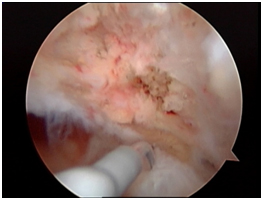

Arthroscopic photos from the surgery show removal of the os. The spinal needle is used to localize the os and demonstrate that it is loose. It is then removed arthroscopically with a burr. Care is taken to not disrupt the dorsal capsule.